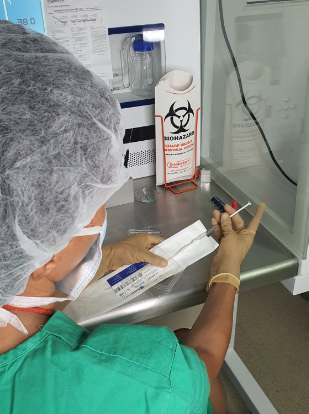

IUI is the process by which sperm that is prepared in the laboratory is transferred directly into the uterine cavity using a special catheter.